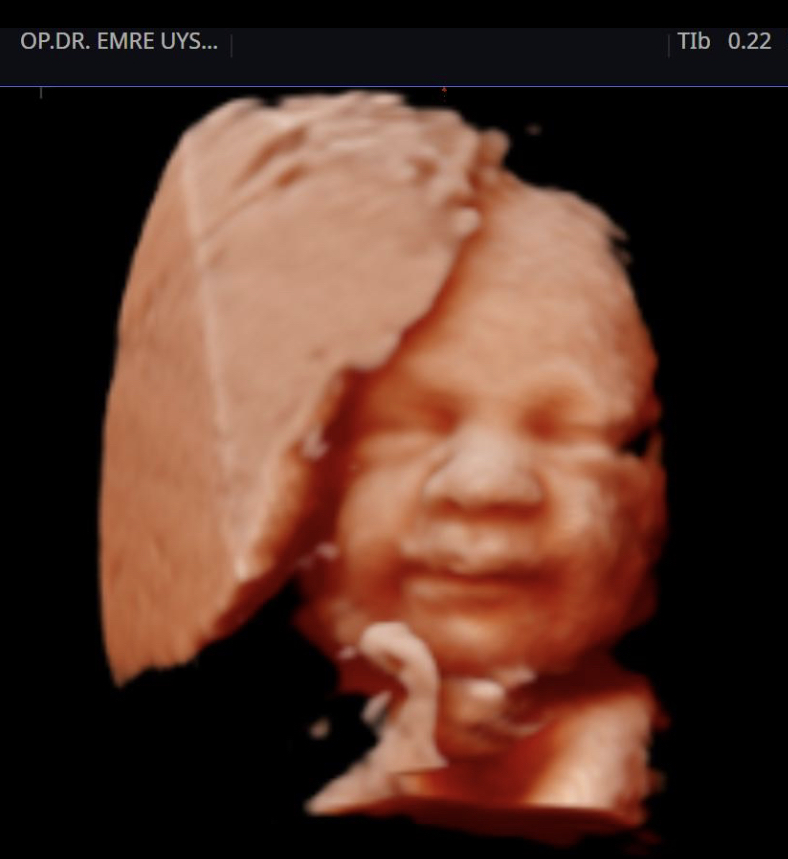

Her kadının hayatında önemli dönüm noktaları vardır. Hiç şüphesizki hamilelik süreci ve doğum bunlardan en kıymetlisidir. Biz de bu değerin farkındayız ve 15 yılı aşan tecrübemiz ile minik mucizenize sağlıkla kavuşma yolculuğunda sizin yanınızdayız. 4d ultrason ile bebeğinizin sağlığını yakından takip ederken, klinik takibimiz ile de süreci eğlenceli ve sağlıklı bir şekilde geçirmeniz için elimizden gelenin en iyisini yapıyor olacağız. Yaşasın Hamilesiniz!